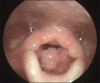

Recurrent respiratory papillomatosis (RRP) is a rare, chronic disease of viral etiology affecting most commonly larynx. A 5-year-old child with stridor was posted for microlaryngoscopic excision of laryngeal papilloma. We discuss the perioperative management of case with the various ventilation strategies. In child with stridor intubation remains the safest option. It is suggested to maintain spontaneous ventilation until intubation as mask ventilation could be difficult.